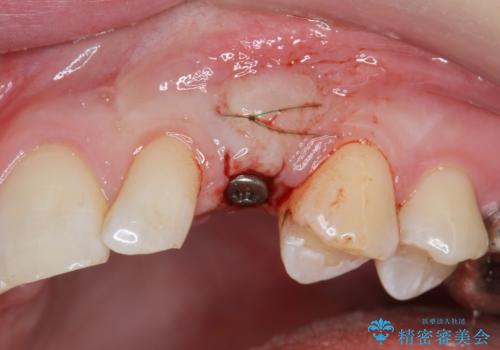

骨造成を伴う 前歯部インプラント治療

- 欠損している前歯のインプラント治療を希望され来院されました。

適切なインプラント埋入を行い、不足している骨量を補うため骨の造成を併用したインプラント治療を計画します。

前歯のインプラント治療は骨量・歯肉の厚み・インプラントの方向をしっかりと計画することで、審美的で長持ちを期待できるような仕上がりとなります。